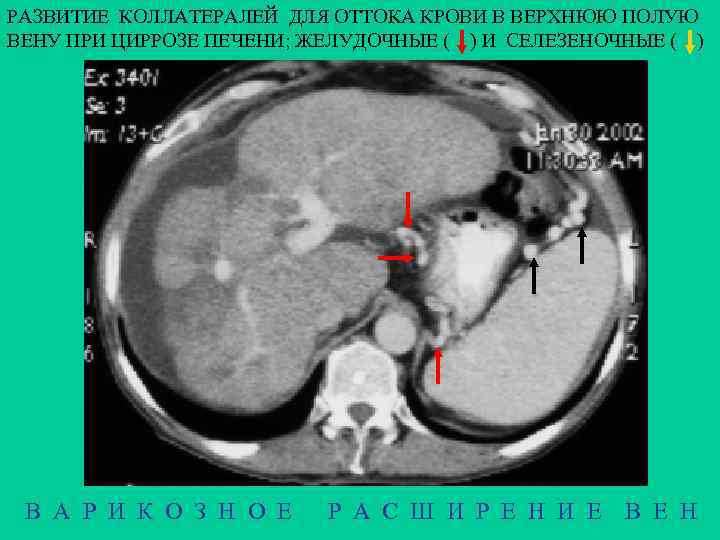

РАЗВИТИЕ КОЛЛАТЕРАЛЕЙ ДЛЯ ОТТОКА КРОВИ В ВЕРХНЮЮ ПОЛУЮ ВЕНУ ПРИ ЦИРРОЗЕ ПЕЧЕНИ; ЖЕЛУДОЧНЫЕ ( ) И СЕЛЕЗЕНОЧНЫЕ ( ) В А Р И К О З Н О Е Р А С Ш И Р Е Н И Е В Е Н

ВАРИКОЗНОЕ РАСШИРЕНИЕ ВЕН ПИЩЕВОДА 8% ВСЕХ ВСКРЫТИЙ МОРФОЛОГИЯ Расширение вен в подслизистом слое с образованием узлов. Слизистая истончается и эррозируется. В своде желудка варикозные вены появляются раньше, чем в пищеводе, но выявляютс труднее – обычно с помощью эзофагогастроскопии ЭТИОЛОГИЯ 1 - портальная гипертензия (цирроз печени), поражаются свод желудка и нижние сегменты пищевода, 2 - сердечная декомпенсация, поражение пищевода на всем протяжении 3 - сдавление верхней полой вены, поражаются верхние сегменты 4 - врожденные расширения КЛИНИКА - кровотечение (для всего ЖКТ: 1 место - язва, 2 - рак, 3 – варикозные вены) Rg Множество краевых дефектов наполнения различной формы и размеров. Рельеф деформирован. При пробе Вальсальвы узлы уменьшаются, при пробе Мюллера - увеличиваются В А Р И К О З Н О Е Р А С Ш И Р Е Н И Е В Е Н